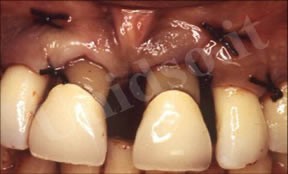

L’ Unità Operativa di Parodontologia e Igiene Orale si compone di 5 sezioni. L’attività’ clinico-assistenziale è svolta da diversi odontoiatri, supportata da igienisti dentali e assistenti alla poltrona, ed è articolata sulla base di appuntamenti programmati. Nell’Unità Operativa di Paradontologia e Igiene Orale del DSMOB si eseguono le seguenti prestazioni odontoiatriche: istruzioni d’igiene orale, ablazione tartaro, full radiografico, terapia dell’alitosi, levigatura radicolare, chirurgia parodontale riparativa, resettiva e rigenerativa e chirurgia plastica dei tessuti molli parodontali.